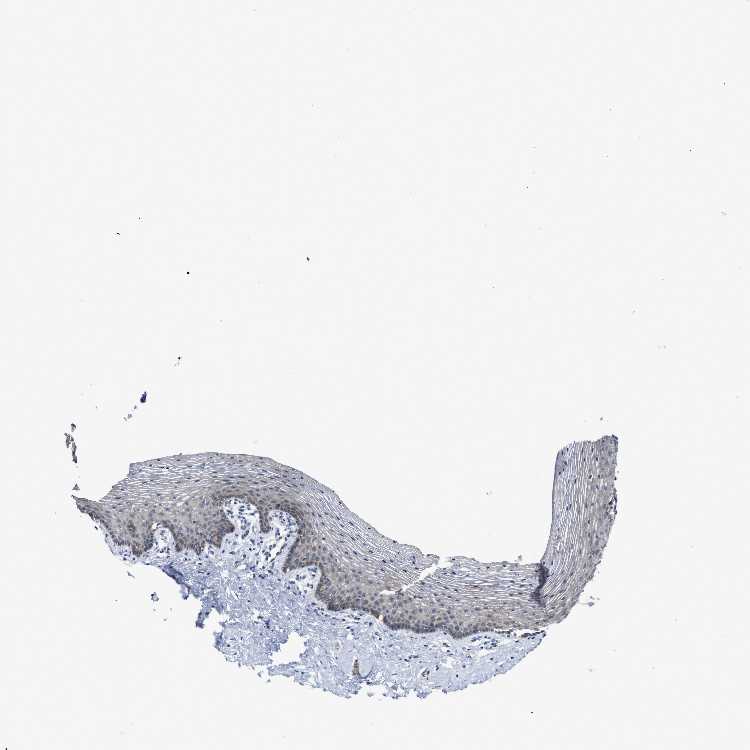

VAGINA - Antibody stainingi

Antibody staining in the annotated cell types in the current human tissue is reported as not detected, low, medium, or high, based on conventional immunohistochemistry profiling in selected tissues. This score is based on the combination of the staining intensity and fraction of stained cells.

Each image is clickable and will lead to virtual microscopy that enables deeper exploration of all samples and also displays staining intensity scores, fraction scores and subcellular localization as well as patient and tissue information for each sample.

Antibody HPA018670Antibody HPA019570

Squamous epithelial cells Not detectedNot detected